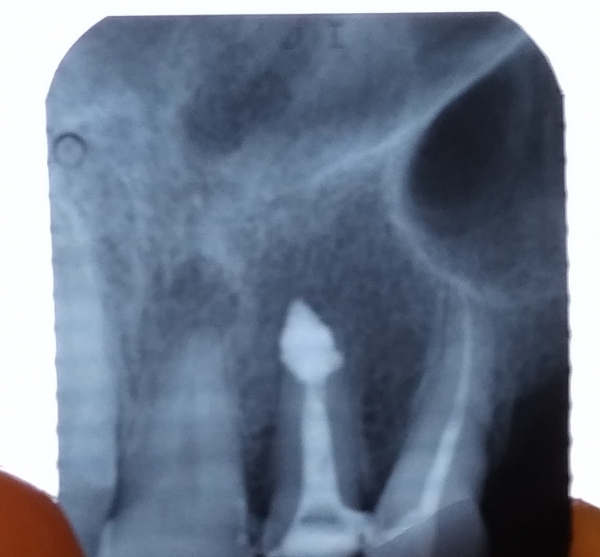

Выведение материала при пломбировании корневых каналов в носовую пазуху.

Пломбировочный материал в Гайморовой пазухе и что с этим делать. В конце готовлю плов ))))